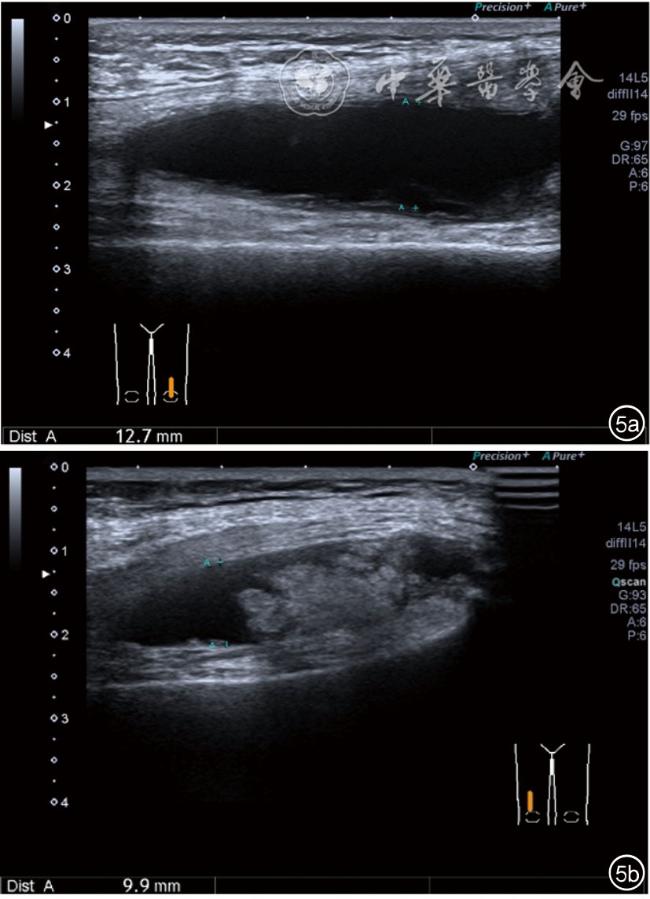

1.关节内表现。(1)骨改变。表现为骨末端或关节周缘出现的骨质局部突起改变,其后方伴或不伴有声影,多见于膝关节内侧缘和外侧缘(图1)。(2)软骨改变。股骨关节面改变可以在长轴及短轴切面显示,嘱患者屈曲膝关节,足平置于检查床,股骨滑车及股骨髁上半部分的关节面即可轻松显示。超声探查可见股骨负重面关节软骨发生不同程度的改变,轻者关节软骨浅侧边界模糊,重者可见关节软骨薄、缺失,软骨下骨缺损改变(图2)。(3)半月板外突。一般内侧半月板突出多见,外侧半月板突出比较少。半月板可见不同程度的外突,同时伴有膝内侧副韧带向外移位(图3)。半月板外周缘性滑脱是指半月板突出超出胫骨平台边缘的距离≥3 mm,其可引起一系列临床症状,早期诊断、早期治疗可以预防骨关节的进一步损伤。(4)交叉韧带损伤。可见前后交叉韧带增粗,回声减低(图4)。(5)髌上囊积液。膝关节是最容易发生积液的关节之一。患者仰卧位,关节积液最常见于膝关节上外侧,因为关节囊向髌股关节上外侧突出。髌上囊积液采用10~18 MHz的高频线阵探头于股四头肌腱纵断面及横断面扫查均可显示,探头频率取决于患者体型。超声可见低回声积液,慢性可伴有丛状滑膜增生(图5)。(6)脂肪垫水肿。脂肪垫在髌骨附着点处回声增强、增厚(图6)。

图5 髌上囊积液、滑膜增生超声图像

3.超声半定量评估。(1)骨赘超声半定量评估:患者仰卧位,膝关节伸直,探头纵切面置于膝关节内侧与外侧,自前向后移动探头以进行全面扫查。测量骨赘的厚度,并进行半定量分析。0级:无骨赘;1级:小骨赘,厚度<2 mm;2级:中等骨赘,厚度2.1~4.0 mm;3级:大骨赘,厚度>4.0 mm。(2)关节软骨超声半定量评估:患者仰卧位,膝关节完全屈曲。探头置于骨上方,检查股骨内侧髁、外侧髁和股骨滑车处关节软骨三个部位,分别进行横切面和纵切面检查,从近侧向远侧做全面扫查。检查时声束要垂直于股骨表面。关节软骨可按病变严重程度分为四级。0级:关节软骨呈均匀的无回声带,其浅侧和深侧边界清晰。1级:关节软骨浅侧边界不清和(或)内部回声增高。2级:①2A级,关节软骨局部变薄,缺损厚度<50%;②2B级,关节软骨局部变薄,缺损厚度>50%,但<100%。3级:关节软骨局部完全消失,伴或不伴有软骨下骨病变。(3)半月板突出分度:半月板外周缘与胫骨平台边缘之间的距离≥3 mm的突出视为病理变化,诊断为半月板周缘滑脱。按照突出程度分为三度:Ⅰ度,半月板外周缘与胫骨平台边缘之间的距离3~5 mm;Ⅱ度,半月板外周缘与胫骨平台边缘之间的距离>5~8 mm;Ⅲ度,半月板外周缘与胫骨平台边缘之间的距离8 mm以上。